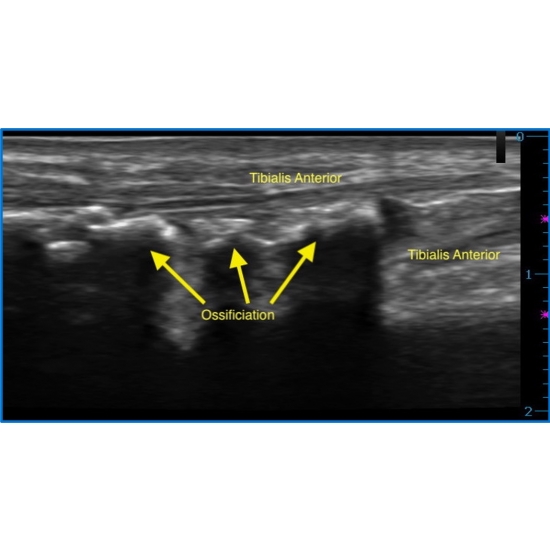

| A Pop At The Anterior Shin During Calf-raises Resulting In A Mobile Mass - Page #3 | |||